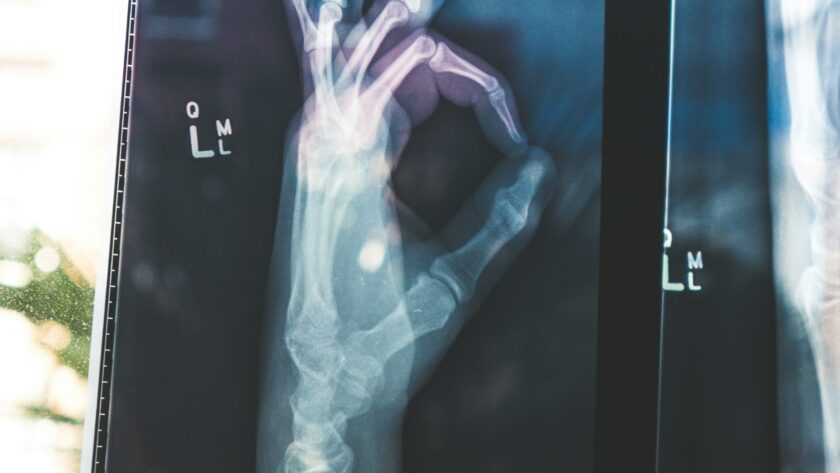

La perimenopausia, un periodo crucial en la vida de la mujer, no solo involucra cambios

hormonales, sino que también puede traer consigo una serie de transformaciones en la

salud musculoesquelética. Durante esta etapa, las mujeres son más propensas a sufrir

dolencias articulares, disminución de la densidad ósea, y problemas de movilidad, lo cual

puede afectar su calidad de vida de manera significativa.

La perimenopausia es un período de transición que puede durar varios años antes de la

menopausia, caracterizado por la fluctuación en los niveles de estrógeno. Este cambio

hormonal tiene un impacto directo en los huesos y las articulaciones. La disminución de

estrógeno favorece la pérdida de masa ósea, lo que aumenta el riesgo de osteoporosis y

fracturas. Además, el debilitamiento de los músculos y ligamentos puede generar dolor y

limitaciones en la movilidad, afectando actividades cotidianas y la calidad de vida.